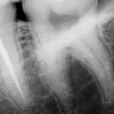

3/3 Postoperative x-ray Glide path with One G, Preflaring with One flare, Shaping with One curve in three waves up to the apex.